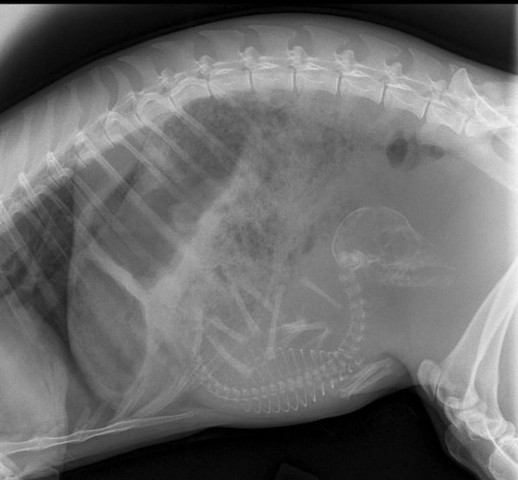

Մենք բոլորս լավ պատկերացնում ենք, թե ինչպես է անցնում մարդու հղիությունը, և շնորհիվ ժամանակակից տեխնոլոգիաների՝ կարող ենք տեսնել երեխային մայրիկի արգանդում հղիության ամենավաղ փուլում։ Իսկ ինչպե՞ս է ընթանում կենդանիների հղիությունը։ Մասնագետները, ովքեր հոգ են տանում հղի կենդանիների մասին, ներկայացրել են նրանց ռենտգենային և ուլտրաձայնային լուսանկարները, որոնք ձեր դատին է հանձնում «twizz.ru» կայքը։

Կատու